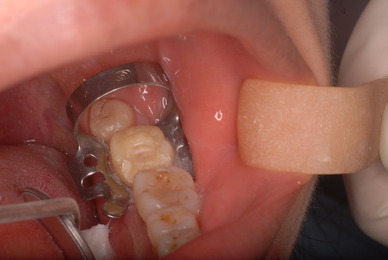

![11937438_965331040210215_3828618638394134229_n[1]](https://livedoor.blogimg.jp/netdental/imgs/d/0/d0817dcf-s.jpg)